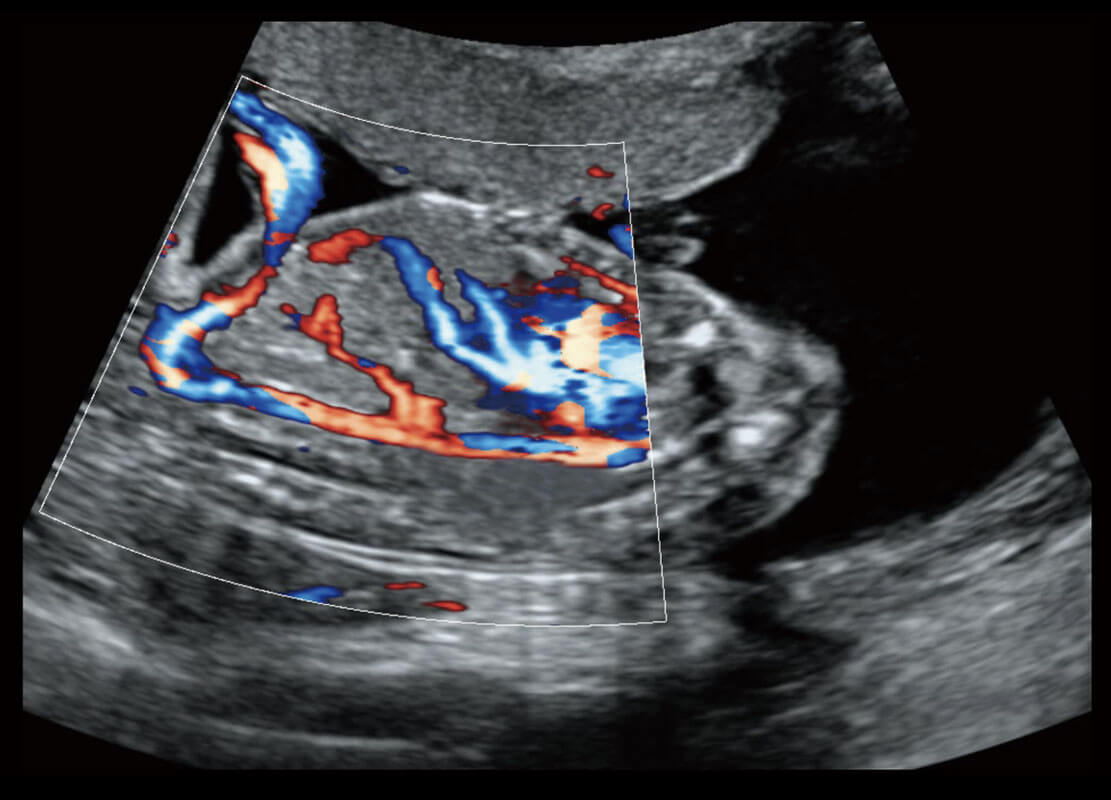

胎心筛查

P60搭载一系列胎儿心脏成像技术,实现精细的胎儿心脏评估。

• 四腔切面

• 四腔心血流

• 右室双出口

• 胎心容积成像

P60搭载宽频带线阵探头、宽景成像、弹性成像技术,为您提供乳腺应用方案。P60支持高频相控阵探头、线阵探头、腹部高频探头、腹部微凸探头等,丰富的探头群搭载敏感的彩色血流成像,适用于新生儿多种脏器检测要求,满足新生儿筛查需求。

• 新生儿肝血管癌

• 新生儿心脏